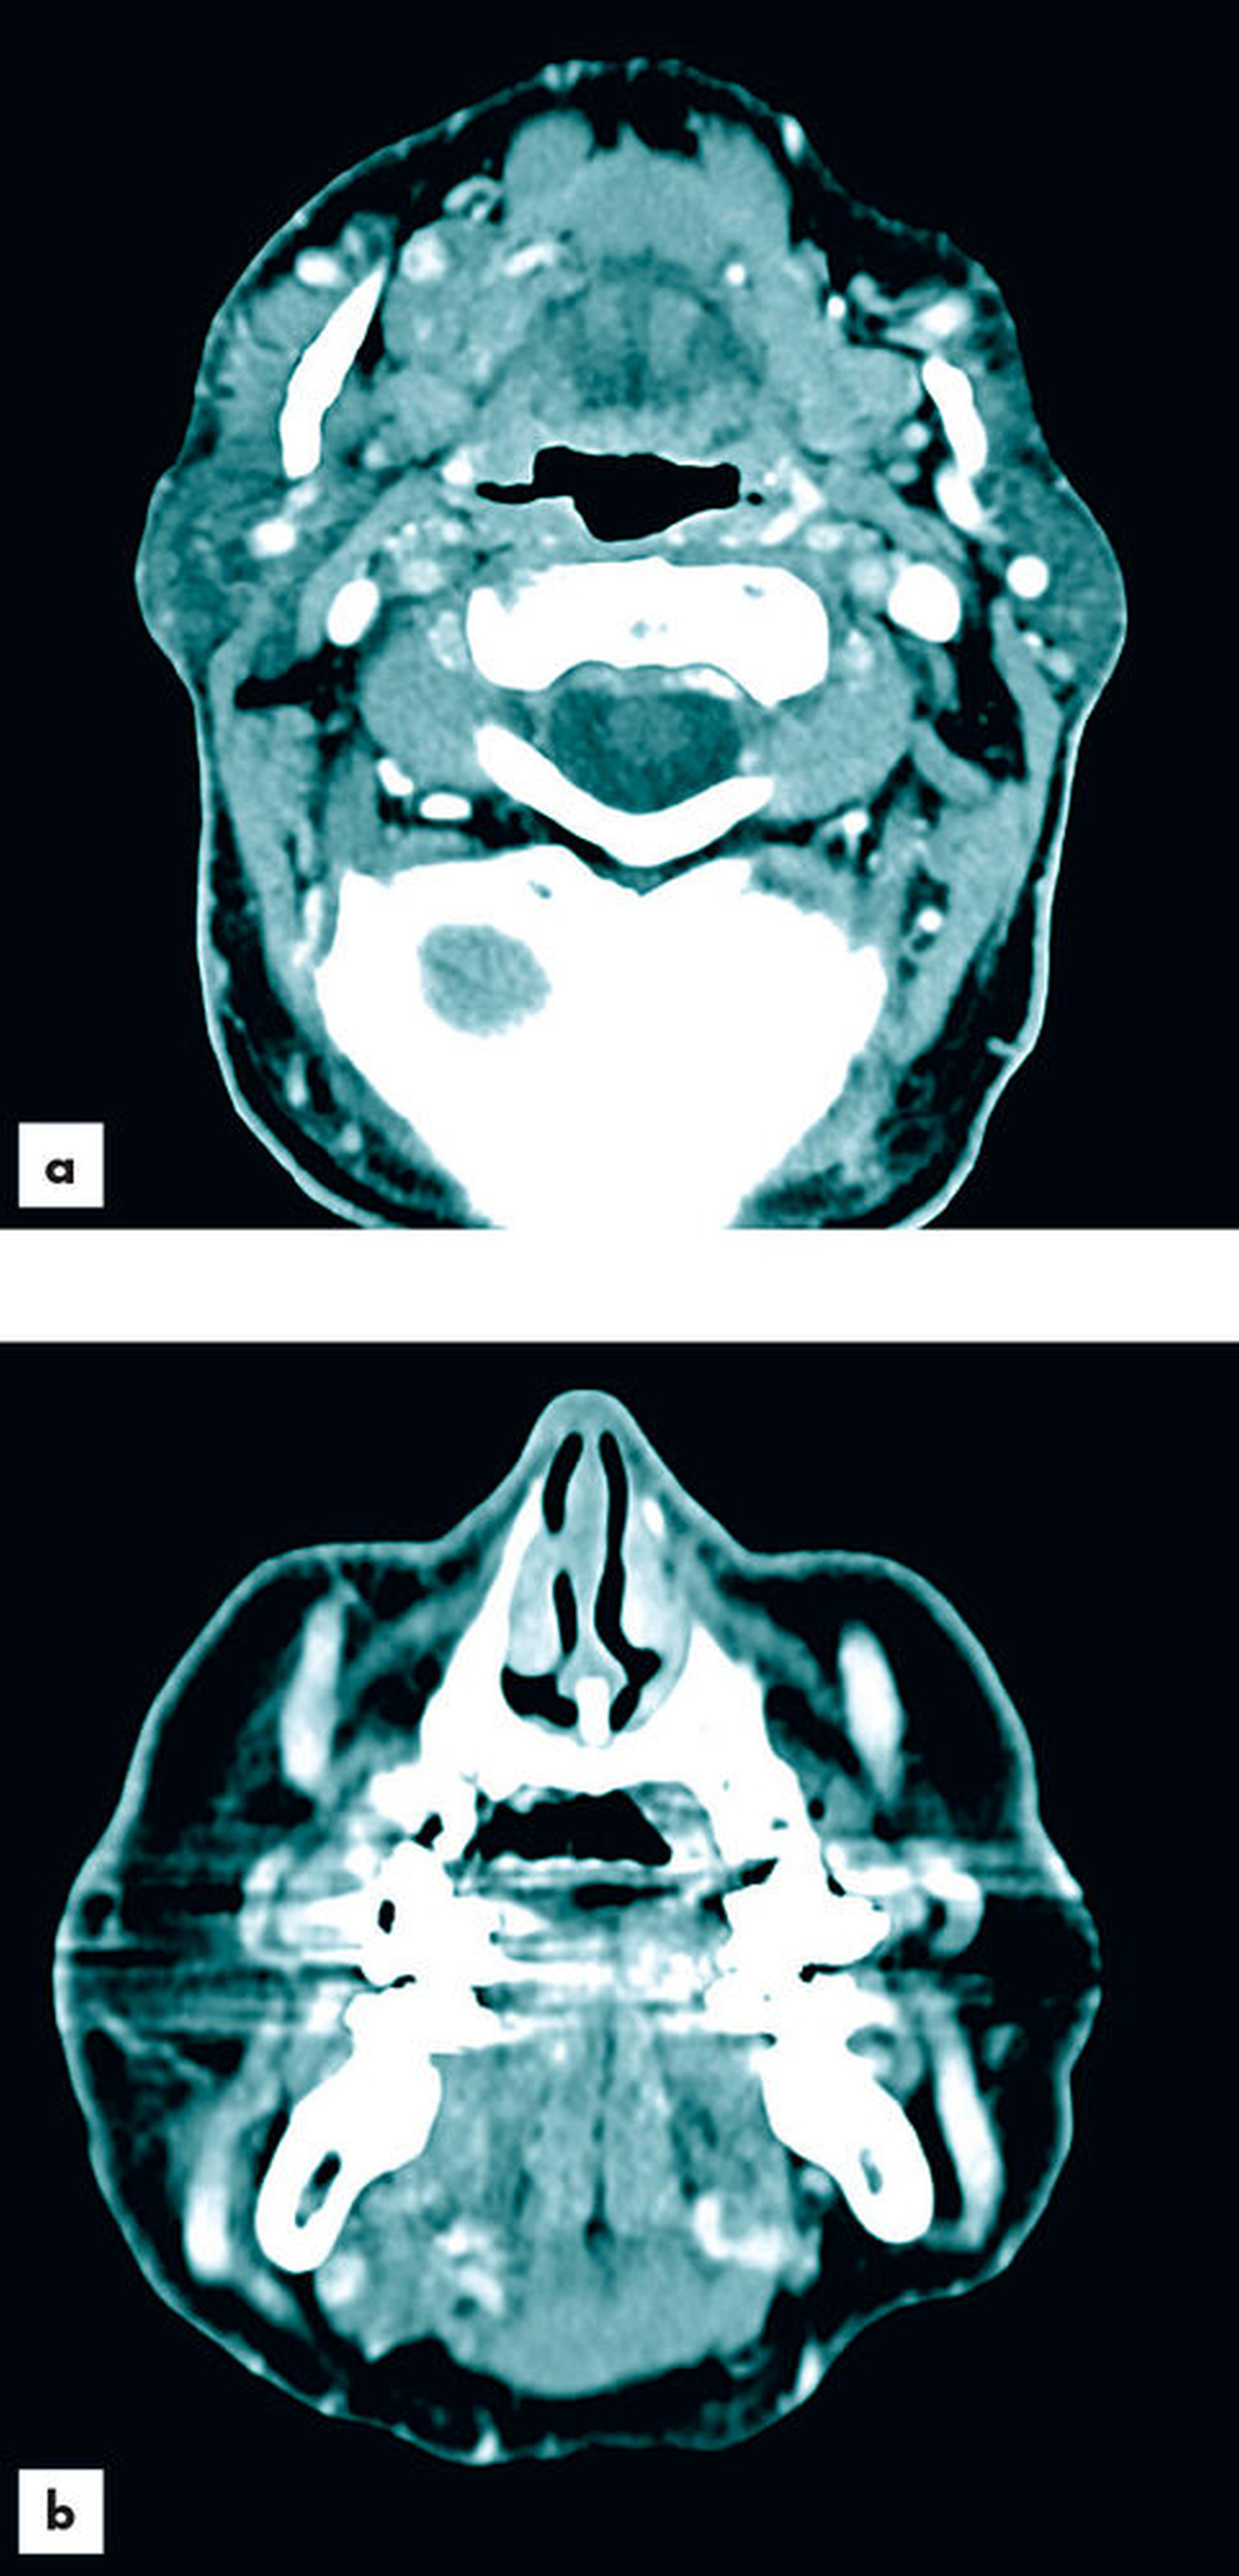

Zur aktualisierten Diagnostik wurde ein Kontrastmittel-CT (Abbildungen 2 und 3) durchgeführt, bei dem neben der bereits bekannten Raumforderung der Glandula parotis links ebenfalls Raumforderungen in der Glandula submandibularis und der Glandula sublingualis rechts festgestellt wurden. Das CT wies im Bereich der Parotis multifokale hypodense, zystische Komponenten sowie dünne Wände und Septen auf. Die Ausdehnung der Neoplasie erstreckte sich bis in die tieferen Anteile des Drüsenparenchyms. Verkalkungen waren nicht nachweisbar und die Kontrastmittelaufnahme erwies sich als moderat. Die Glandula submandibularis und die Glandula sublingualis rechts imponierten ebenfalls durch unklare Kontrastmittelaufnahme. Bildmorphologisch bestand kein Hinweis auf Malignität. Nebenbefundlich lag bildmorphologisch eine chronische Sinusitis maxillaris mit dentogenem Fokus 26 und 27 vor. Die radiologische Verdachtsdiagnose lautete: Verdacht auf bifokalen Warthin-Tumor und bildmorphologisch nicht eindeutig einzuordnende, aber verdächtige Veränderungen der Glandula submandibularis und der Glandula sublingualis rechts.

Bildmorphologisch sind Warthin-Tumore von einer Kapsel umschlossen und erreichen durchschnittlich eine Größe von 3 bis 4 cm [Donath und Ussmüller, 2020]. Im CT zeigen die Raumforderungen hypodense Dichtewerte mit anteilig zystischen Veränderungen [Kloth et al., 2015]. Es treten dünne Wände und Septen auf, wobei es nicht zu Verkalkungen kommt [Janssen et al., 2010].